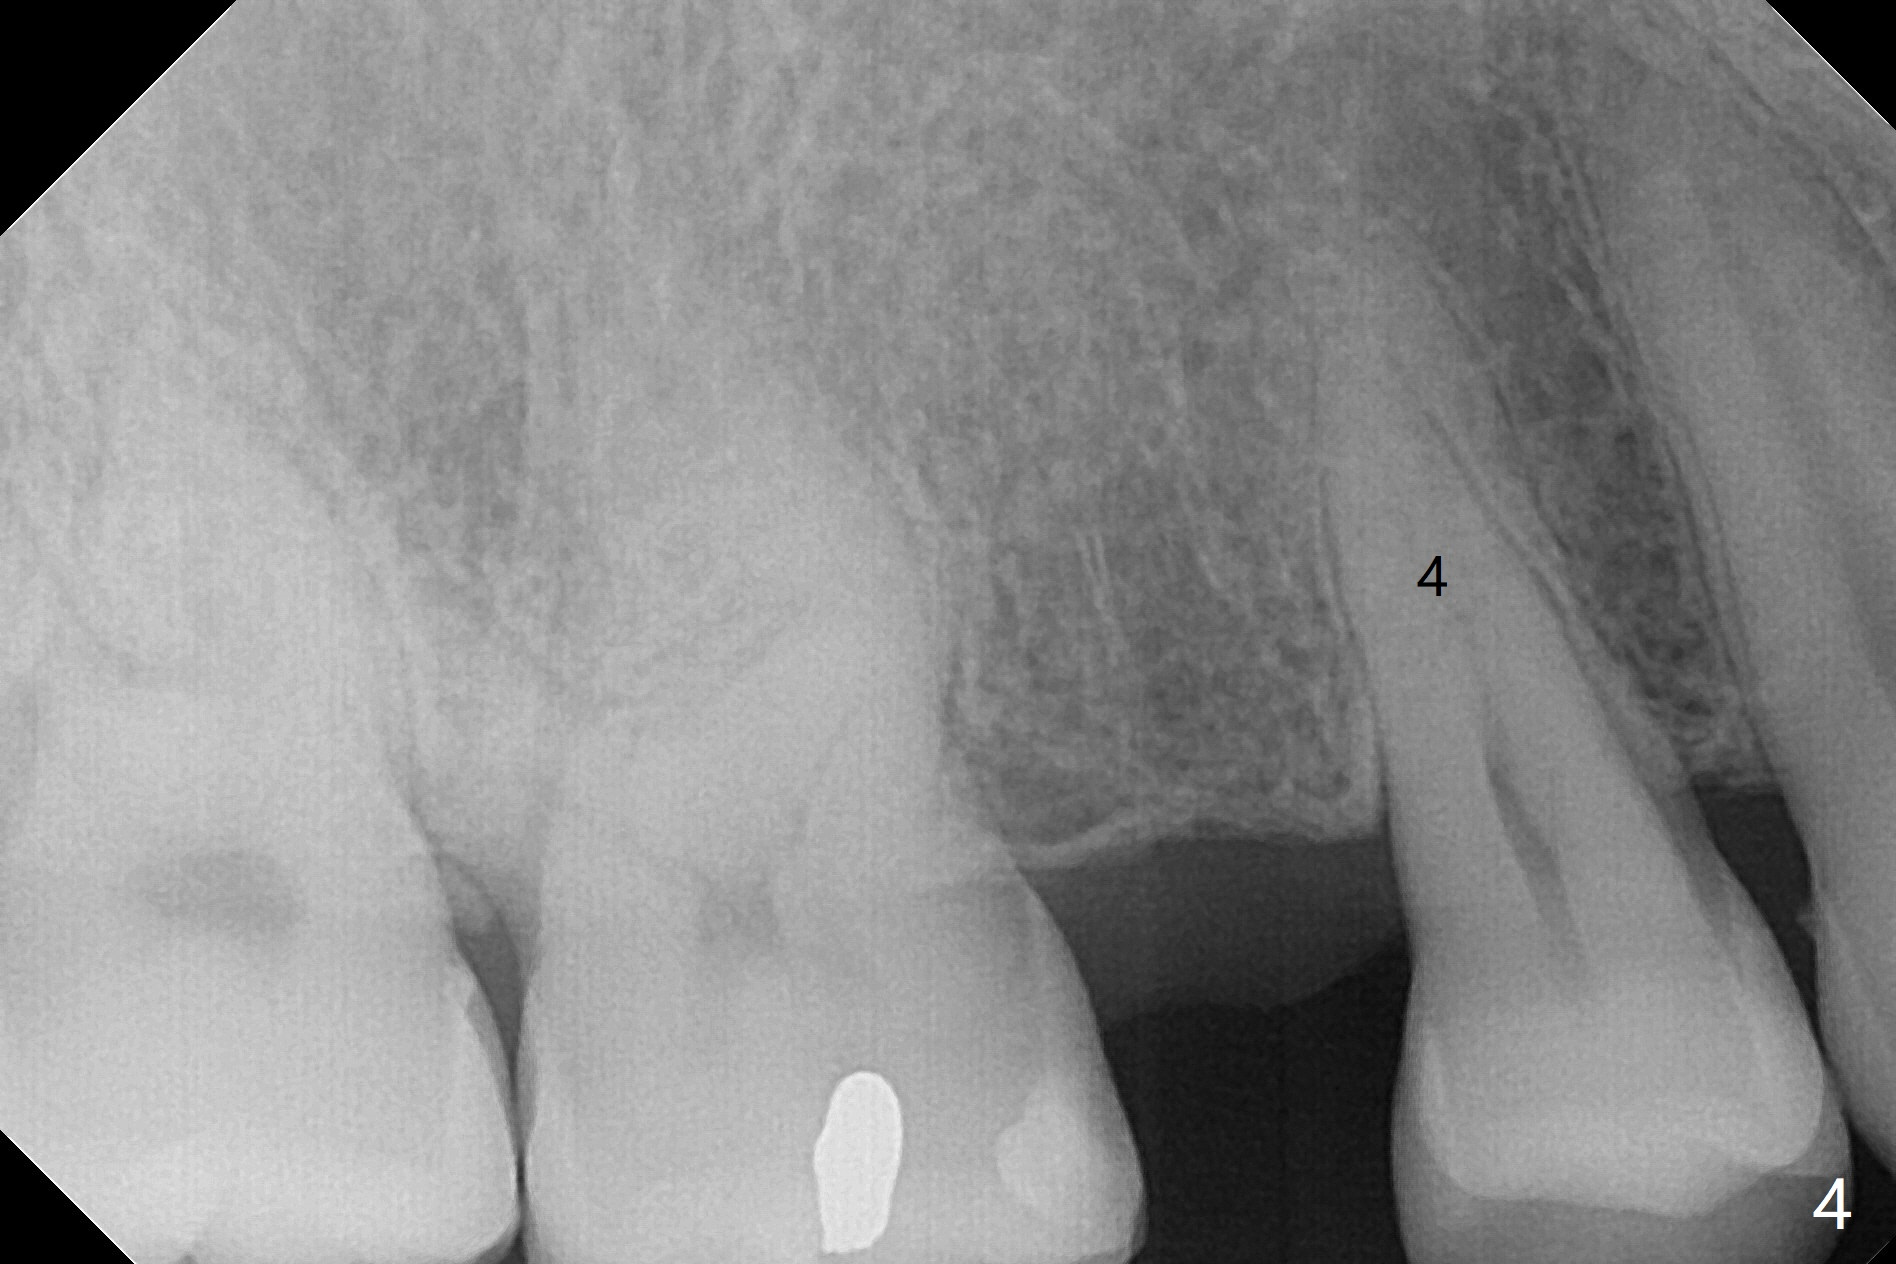

A 40-year-old man requests orthodontics after #17 and 32 extraction. UL5 is missing (Fig.1), while the upper midline deviates to the left (Fig.2 arrow) with crowding between UL2 and 3 (Fig.3). The main goal is to retract UL5 distal and move the upper midline to the right to alleviate UL anterior crowding. Implant will be not needed. To monitor potential root resorption associated with tooth movement, preop PAs are taken (Fig.4-7). The space for an implant at UR5 is narrow. UR4 needs to be distalized using UR7 or a miniimplant distal to UR7 as an anchor (Fig.8). UR4 and 3 will be repositioned to establish Class I occlusion (Fig.9). The space gained by UR4 distalization may be enough to correct the upper midline deviation and UL3 malposition (Fig.10). Brackets will be placed in the lower arch in spite of the normal alignment (Fig.11). UL2 and 3 brackets are unable to be engaged to 14 niti wire (Fig.12). Next visit try to engage UL2 bracket. If not, save the old wire for possible future reuse. Closed spring is placed with 18 ss wire <3 months post banding (coronavirus). Three weeks post closed spring between UR4-7, UR3,4 are being distalized (Fig.13). Distalization of UR4 is not much in 5.5 months (Fig.14,15). It seems necessary to use a miniimplant distal to UR7 as an anchor (Fig.16 white circle), place a long hook mesial to UL4 (more or less root movement instead of tilt) and place the same closed spring between the anchor and hook. In spite of the fact that UR4 seems to have been completely distalized and that UR2 is being distalized 8 months post banding (Fig.18), a 8 mm long mini-implant is placed in the maxillary tuberosity with minimal local anesthetic (Fig.17,19). A longer closed spring (18 mm) is placed between the implant and UR3 hook (Fig.20). Next appointment a lingual button will be placed at UR4 for rotation, while a post hook mesial to UR3 for torque. UR3 distalizes with the help of UR mini-implant, which is unfortunately loose. Next visit place lingual button at UR4 (Fig.21 arrow) to distalize the lingual cusp. Crimpable power hook is placed mesial to UR2 for distalization (for root torque, Fig.22). If it works, remove the wire and reposition the hook for UR1 next visit. UR2 is distalized in one appointment (~ 1 month, Fig.23, as compared to Fig.22). With lingual button at UR4, rotation seems to have been corrected shortly (Fig.24 arrow).